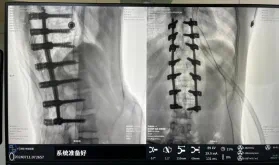

¾ÝϤ¼¹Öù²àÍäÊÖÊõÖÎÁƺó¿ÉÒÔ¼á³ÖÇû¸Éƽºâ£¬¸ÄÉÆÍâ¹Û²¢±ÜÃâ»ûÐνøÒ»²½Éú³¤¡£»¼ÕßµÄÉúÑÄÖÊÁ¿»ñµÃÌá¸ß£¬½ø¶øïÔ̼¹ÖùÌ«¹ý»ûÐοÉÄÜ´øÀ´µÄ¼²²¡µÄ±¬·¢ÂÊ£¬Íâ¹ÛÉÏµÄÆð¾¢×ª±äÍùÍùÒ²ÄÜ´øÀ´»¼ÕßÐÄÀíÓ뾫ÉñµÄÆð¾¢×ª±ä¡£ÁÙ´²ÉÏ»á×ÛºÏ˼Á¿»¼ÕßµÄÄêËê¡¢²àÍäˮƽ¡¢Ï£ÍûÇ÷ÊÆ¡¢¹ÇÖÊÌõ¼þ¡¢Ïà½ü½Ú¶ÎÇéÐΡ¢ÊÖÊõ½Ú¶ÎµÈÒòËØ£¬ºÏÀí½ÓÄɸöÐÔ»¯µÄÊÖÊõ·½·¨¾ÙÐÐÖÎÁÆ¡£È»¶ø£¬ÓÉÓÚ¼¹ÖùÉñ¾Ñª¹ÜÃܲ¼£¬ÊÖÊõ²Ù×÷Ïà¶ÔÖØ´ó£¬ÊÖÊõÄѶȸߡ¢Î£º¦´ó£¬¹Å°å¼¹Öù²àÍäµÄÊÖÊõ·½·¨ÍùÍùÓнϸߵÄÉñ¾»ò¼¹ËèËðÉËΣº¦¡£¹Ê´Ë´Î¿ÆÊÒ¾öÒ鿪չ»úеÈ˸¨Öúµ¼º½Ï¼¹Öù²àÍä½ÃÐΡ¢Ö²¹ÇÈÚºÏÄÚÀο¿ÊÖÊõ¡£Êõǰ£¬Ò½ÉúÍŶÓÔÚ»úеÈ˶àά¶ÈͼÏñÈÚºÏÖÇÄÜÊÖÊõÍýÏ빦ЧµÄ¸¨ÖúÏ£¬Ô¤ÏÈÍýÏëÁËÀíÏëµÄÖö¤Â·¾¶¡£ÊõÖУ¬Ììçá¹Ç¿ÆÊÖÊõ»úеÈË׼ȷ×ñÕÕÊõǰÍýÏ룬ƾ֤Åä׼Ч¹û£¬ÊµÊ±¶¨Î»²¢×¼È·Ö´ÐÐÖö¤²Ù×÷£¬ËùÓе¼Õë¾ùÓõç×êÖÃÈ룬һ´ÎÐÔÀֳɣ¬ÐÖúÒ½Éú˳ËìÍê³ÉÊÖÊõ¡£×îÖÕ£¬ÔÚÂé×í¿Æ¡¢ÊÖÊõÊÒÇ×½üÅäºÏÏ£¬Àúʱ3СʱÀÖ³ÉÍê³É²àÍä½ÃÐÎÊõ£¬³öѪÁ¿½ö500ml¡£Êõºó£¬»¼Õ߻ָ´ÓÅÒ죬¾Þϸ±ã¼°ÏÂÖ«Éñ¾Ô˶¯¸ÐÊÜÕý³£¡£

ͼΪÖö¤ºó

´Ë´ÎÔÚ³ä·Ö°ü¹Ü»¼ÕßÇå¾²ºÍÊÖÊõЧ¹ûµÄÌõ¼þÏÂʹÓûúеÈ˸¨ÖúÏÂÊÖÊõµÄÀÖ³ÉʵÑ飬´ó´ó½µµÍÁ˸ßÄѶÈÊÖÊõµÄΣº¦£¬²¢½øÒ»²½¼õÇáÁË»¼ÕßÊÖÊõ´´ÉË¡¢Ëõ¶ÌÁË¿µ¸´Ê±¼ä¡£ÕâÒ²±ê¼Ç×ÅÄÏ·½Ò½Ôº¸ÓÖÝÒ½Ôº¼¹ÖùÍâ¿ÆÖÎÁƸöÐÔ»¯¡¢¾«×¼»¯¡¢ÖÇÄÜ»¯Ë®Æ½½øÒ»²½ÌáÉý¡£